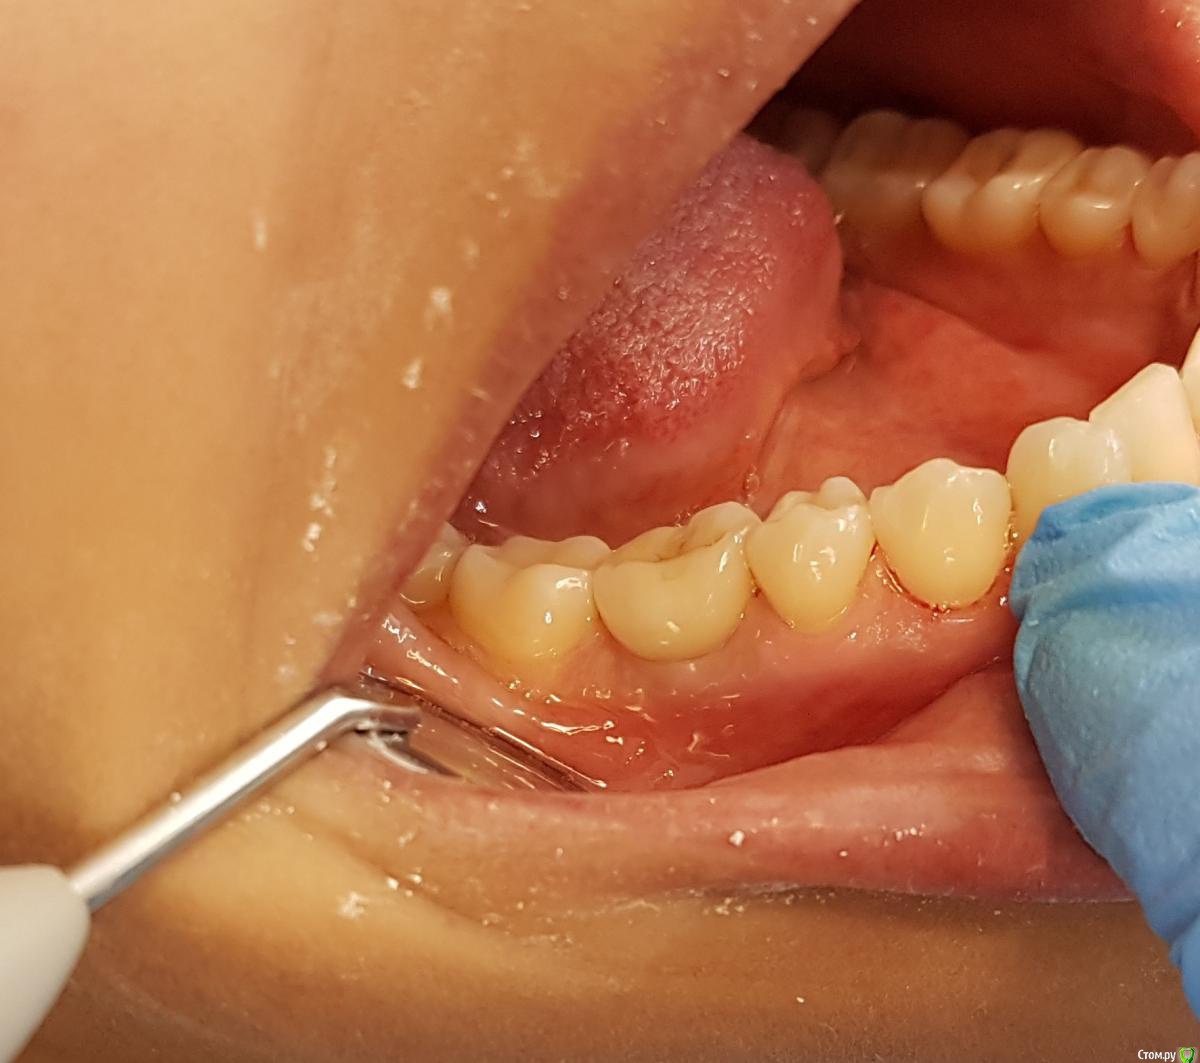

Kostoprav Опубликовано 24 мая, 2016 Поделиться Опубликовано 24 мая, 2016 удалил, вкрутил,графт gen oss, фдм.P.S. сори за плагиат) 3 Ссылка на комментарий